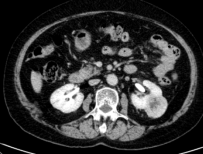

广泛开展腹腔镜下肾癌根治术、肾盂癌根治术、肾部分切除术、肾肿瘤剜除术、肾上腺肿瘤切除术、肾盂输尿管成形术、肾囊肿去顶减压术、输尿管上段切开取石术等。全腔镜下进行,创伤小、恢复快。 腹腔镜肾肿瘤剜除术(保肾) 腹腔镜肾癌根治术腹腔镜肾盂癌根治术